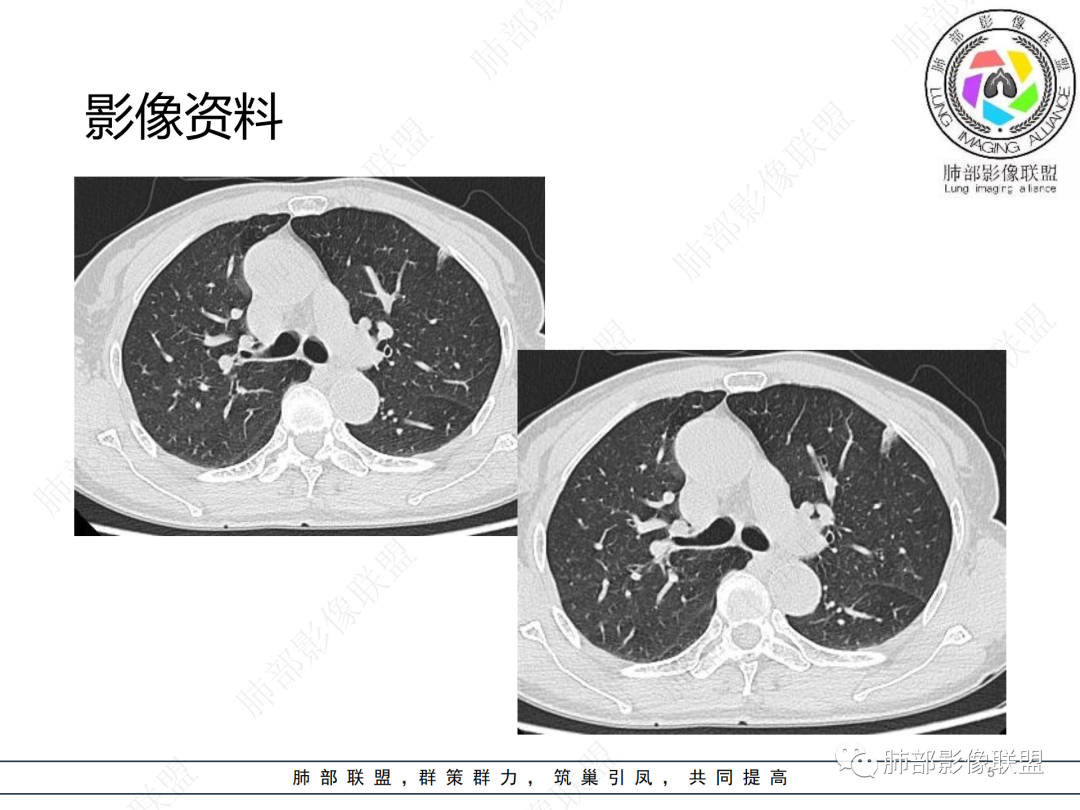

中年女性,咳嗽,胸部CT左肺上叶长条状实变影,周围磨玻璃影,边界清楚,病灶近端似乎有点状高密度影,首先考虑炎性肉芽肿,其次腺癌待排

晨读病例,中年女性,咳嗽一年,左肺上叶胸膜下三角形阴影,局部收缩,周围边缘清晰的磨玻璃影,考虑炎性病变,OP。鉴别腺癌。

左肺上叶胸膜下混合磨玻璃结节,边界似清非清,其内可见增粗血管,抗炎效果差,1年复查增大,考虑粘液腺癌,鉴别慢性炎症

左肺上叶实变影伴磨玻璃影,边界清楚,考虑腺癌,

晨读:慢性病程,胸膜下,边界似清不清,粘液腺癌。

左肺上叶磨玻璃密度,血管增粗,边界清,考虑腺,鉴别炎性

晨读,左肺上叶胸膜下混合磨玻璃密度影,内部可见血管增粗,抗炎治疗效果不佳,一年复查增大,考虑腺癌可能

晨读 左肺上叶胸膜下条片状混杂密度影,膨胀及收缩不明显,周围磨玻璃影边缘似清非清。胸膜糊墙,复查较一年前病灶增大,首先考虑粘液腺癌。

左肺上叶混合磨玻璃病灶,磨玻璃边界似清非清,病灶可见增粗血管,边缘似有月牙征,关键病史与2021年比较有增大,考虑恶性可能大,粘液腺癌、腺癌可能。鉴别慢性炎症。

老年女性,慢性咳嗽,治疗复查无效,咳少量白色粘痰,左肺上叶前段胸膜下亚实性结节,形态呈树上“蘑菇”征,并见“小圆圈”影,周边模糊的磨砂玻璃影,首选粘液腺癌,病灶定位下经皮肺穿刺活检!

晨读:患者,女,65,咳嗽1年,加重1月。胸部CT:左肺上叶胸膜下不规则mGGN,实性灶有膨隆,收缩不明显,周围磨玻璃影似清非清,内可见空泡/细支气管断面?胸膜糊墙。复查较一年前病灶增大。考虑粘液腺癌?鉴别TB、NTM。

晨读左肺上叶胸膜下结节,混合密度磨玻璃,边界似清非清,支气管腔内粘液,警惕粘液腺癌

左肺病灶,周围似清非清,考虑腺癌可能性大,鉴别炎性肉芽肿

左肺上叶混合磨玻璃结节影,部分边缘小叶间隔阻挡,周围磨玻璃影似清非清,内可见空泡,复查较一年前病灶增大。考虑粘液腺癌?鉴别炎性肉芽肿

左肺上叶前段混合磨玻璃结节,实性部分局限性凹陷,磨玻璃影边缘似清非清,老年女性,1年多胸痛病史,考虑腺癌,粘液性腺癌

肺部联盟晨读:老年女性,病程1年,混合磨玻璃密度,周围边缘较清楚,腺癌>炎症

晨读老年女性,左肺上叶胸膜下条状实变影,周围可见絮状磨玻璃影,边界较清,可见小叶间隔阻挡月牙征,抗炎无效,复查增大,考虑腺癌。

左肺上叶结节影,周围边界清楚磨玻璃影,考虑粘液腺癌

左肺上叶胸膜下混合磨玻璃结节,边界不甚清楚,抗炎无效,目前增大,考虑粘液腺癌

左肺上叶混合密度的结节,部分磨玻璃边界偏清晰,内部血管似有增粗,病灶较一年前增大,肿瘤要警惕。

左上叶混杂密度结节,边界似清非清,其内血管影增粗扭曲,年度复查增大,白色粘液痰,有树上蘑菇征?综合分析考虑结节型粘液腺癌

混合磨玻璃结节,密度不均,短毛刺,周围磨玻璃边界较清,复查病灶增大,考虑腺癌,鉴别炎性肉芽肿。

左肺上叶混合结节伴磨玻璃影,边界清楚,考虑腺癌

这个要做个重建就好了  可以整体观察这个病灶 1.边界清  2复查有增大,考虑恶性是有可能的

晨读,混合磨玻璃结节,内见增粗血管影,病史长,结节型粘液腺癌,抗炎后短期复查。